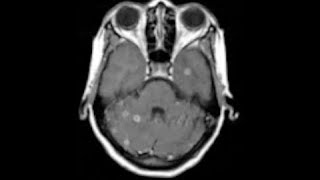

Infectious Diseases Of The CNS - Ayelet ERAN Part 1

7th FRANCE-ISRAEL REVIEW COURSE in RADIOLOGY Specialty : NEURO Speaker : Ayelet ERAN Year : 2014.

Bacterial Meningitis (CNS Infection) – Infectious Diseases | Lecturio

This video “Bacterial Meningitis (CNS Infection)” is part of the Lecturio course “Infectious Diseases” ▻ WATCH the complete course on ...

itskind alike Central Nervous System Infections

Table of Contents: 00:06 - Causes of CNS Infxns 00:08 - Diagnosis 00:51 - Sites of Infection 01:16 - Meningitis vs. Encephalitis 02:06 - Meningitis 02:07 - Clinical ...